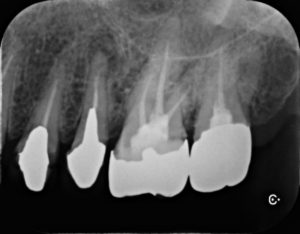

左上奥歯に不適合のクラウンとそれに伴う二次う蝕を認めた。レントゲン診査より根管治療の必要性も認めたため、再根管治療および再修復治療を行うこととした。その他全顎的に歯周炎を発症し、深いポケットを有する部分が多数存在した。

診断:全顎的な慢性歯周炎慢性根尖性歯周炎と二次う蝕

不良補綴物の除去